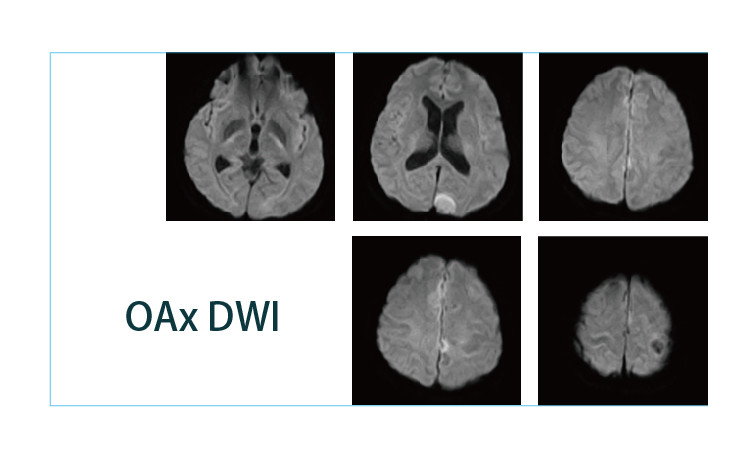

【朗润影像档案】20190426磁共振影像病例结果讨论

【朗润影像档案】磁共振影像病例分享(编号20190426)